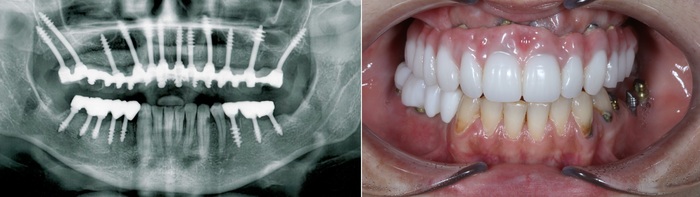

Я не раз говорил, что при корректном протезировании и качественном уходе за полостью рта, с имплантатами, со временем, ничего не происходит. Они как стояли, так и продолжают стоять. А вот то или иное воспаление, которое возникает в области своих зубов, может вовлекать в себя рядом стоящие имплантаты. Очень важно проходить профилактические осмотры, проще говоря ТО, каждые полгода. Это требуется для контроля и выявления тех или иных проблем на начальных этапах. Исправить которые не составит труда.

Интересно ли вам на сколько «попал» пациент только лишь потому, что не соблюдал элементарных вещей и забил на дальнейшее восстановление зубов? Так вот, около 500К. Это сумма выкинутых на помойку денег. Не говоря уже о том, что при повторном протезировании и исправлении сложившейся ситуации ценник будет выше, если не в два, то в полтора раза точно.

Поэтому я призываю вас - не пренебрегайте профилактическими осмотрами у стоматолога. Тем более, если у вас есть те или иные ортопедические конструкции. Этого пиздеца можно было легко избежать, если бы мужчина приходил на плановые приёмы, где доктор проводил бы ТО в виде снятия коронок, их чистки и, как не смешно это звучит, заново учил бы правильно ухаживать за зубами. (К слову - постоянное протезирование никак не умоляет необходимости в профилактических осмотрах)